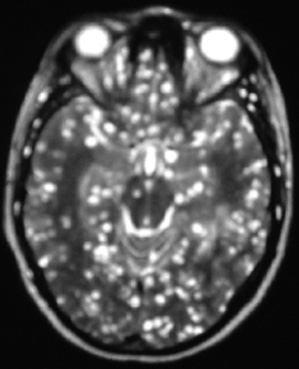

La RM detecta tanto imágenes antiguas como recientes. En T2, pueden dar focos de señales heterogéneas que se confunden con el edema periférico. En T1, se observan zonas hipointensas rodeadas de un halo hipointenso correspondiente al edema periférico (25), que miden entre 1 y 3 cm de diámetro, múltiples en el 85 % de los casos. Captan en anillo la sustancia paramagnética gadolinio. Tienen efecto de masa y se rodean de edema vasogénico, en forma variable. El mayor compromiso es profundo, a nivel de los núcleos basales (75-88 %) y subcortical. El compromiso hemorrágico es raro (25).

En la figura 3, se observa la imagen axial en RM, que muestra compromiso cerebral a base de forma captadora en anillo y rodeado de edema a nivel de los ganglios basales de un paciente inmunodeprimido por VIH/sida.